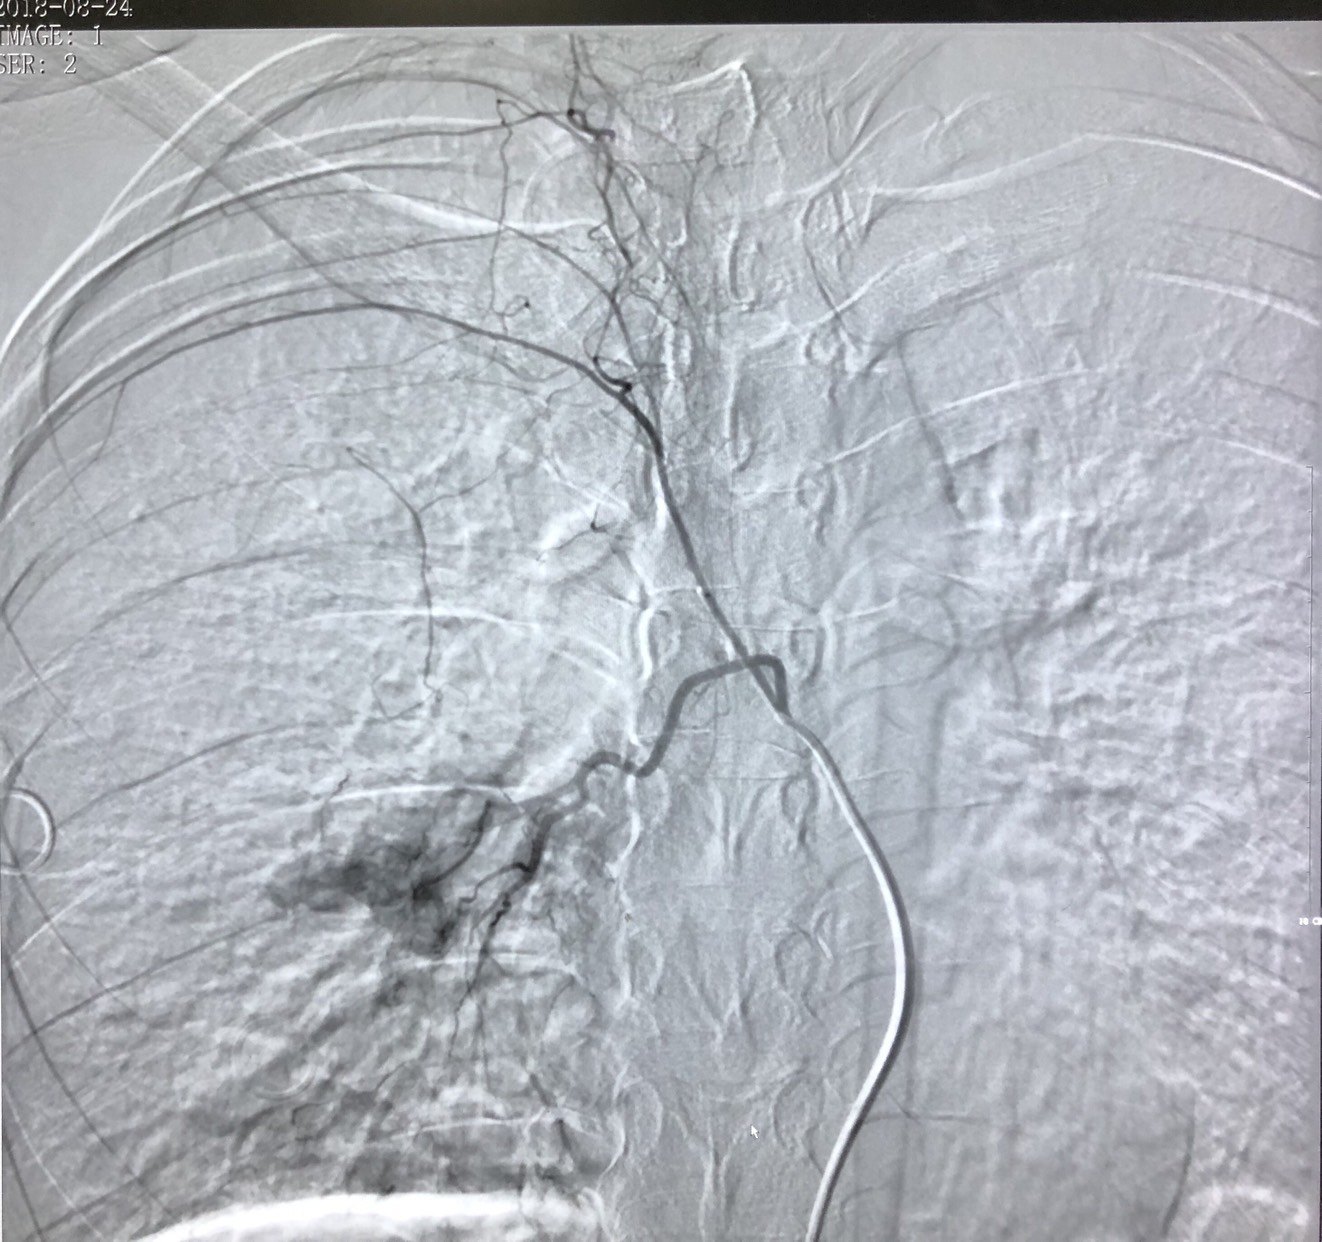

微球栓塞治疗后再次造影右肺肿瘤染色基本消失。

电点评:部分血供丰富的肺转移瘤行经支气管动脉栓塞治疗可减少肿瘤血供,控制肿瘤生长,也可提高后续消融治疗的疗效和安全性,值得大家关注和更多案例的积累。